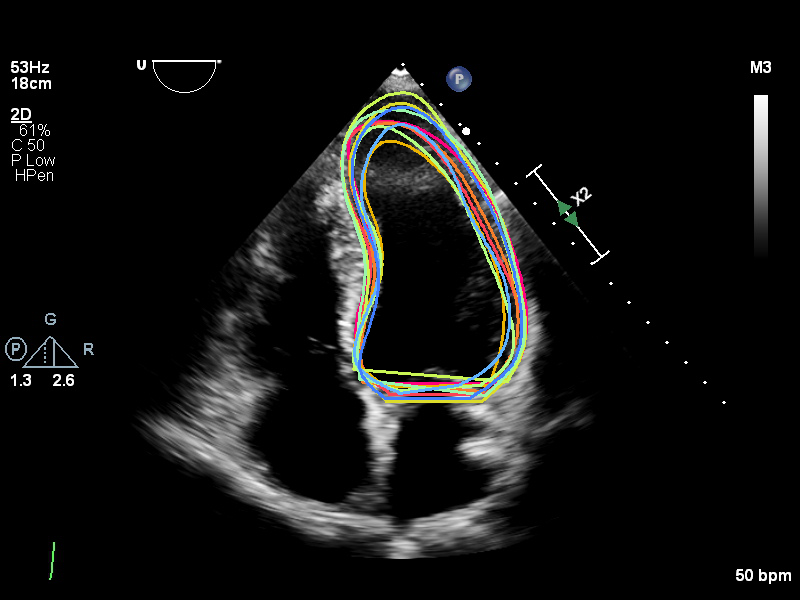

The image on the left illustrates an example of the multi-expert annotations within this dataset, while the corresponding consensus curve is shown on the right.

The Unity web-based, interactive, real-time annotation platform enables clinical experts across the UK to collaboratively and efficiently label medical images. The platform’s intuitive interface allows experts to annotate key anatomical structures with precision, including critical features such as key points and curves along the endocardial border, as illustrated above. The platform’s accessibility and real-time capabilities facilitate large-scale multi-expert annotations, enhancing the quality and accuracy of labelled datasets for medical image analysis.